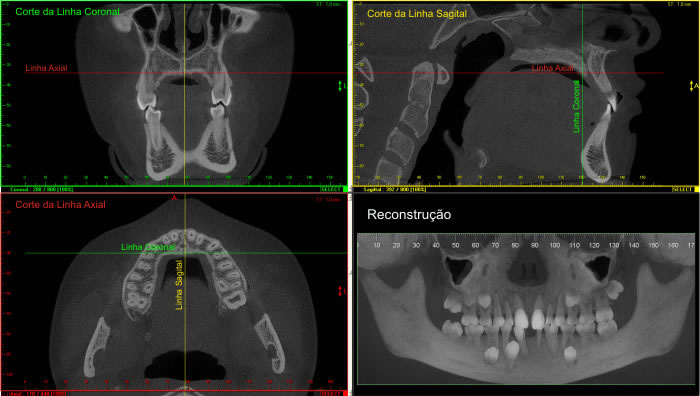

Na apresentação básica, a reconstrução do exame tomográfico aparece como fatias de imagens

nos três planos: coronal, axial e sagital.

O radiologista “navega” por estas imagens, analisando toda a aquisição e com o auxílio de ferramentas ele monta e escolhe as imagens que irão compor o filme.

Nos softwares há ferramentas que permitem a reconstrução e a obtenção de novos cortes que mostram imagens de uso pontual na odontologia como os cortes transversais e longitudinais.

Os cortes transversais são cortes perpendiculares ao arco da maxila e mandíbula.

Na reconstrução panorâmica aparece uma régua no limite inferior que serve de localização para os cortes transversais.

Os cortes longitudinais são cortes no sentido vestíbulo lingual ou palatino, perpendiculares a uma reta traçada sobre o dente ou a área em questão.

1- A reconstrução panorâmica nada mais é que a representação em forma de panorâmica a partir de um arco criado sobre o rebordo, dessa forma, estruturas fora desses limites de reconstrução não aparecerão, diferente da radiografia panorâmica, onde estruturas “fora do foco” aparecem superpostas e por vezes borradas.

2- Nos cortes sagitais o perfil não muda para lado direito e esquerdo, os cortes são seqüenciais.

3- Por vezes utilizaremos a apresentação das imagens em MIP (Projeção de Intensidade Máxima) que dá o aspecto 3D de crânio seco.